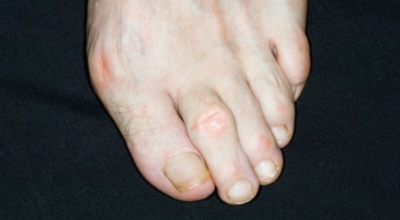

엄지발가락 통증 - 내성발톱

정확한 질환명은 조갑감입증으로 발톱이 살을 파고들어 가면서 부종과 염증을 일으키는 질환입니다. 발병초기에는 간혈적 통증 정도지만 염증과 부기가 악화되면 발을 내딛기 조차 힘든 심각한 통증에 시달리게 돼요. 문제는 내성발톱으로 병원을 찾는 수가 적다는 것입니다. 현대인의 생활형 족지 질환인 내성발톱은 누구나 겪을 수 있는 만큼 통증을 참지말고 병원에 가서 적극적인 치료를 받아야 해요.